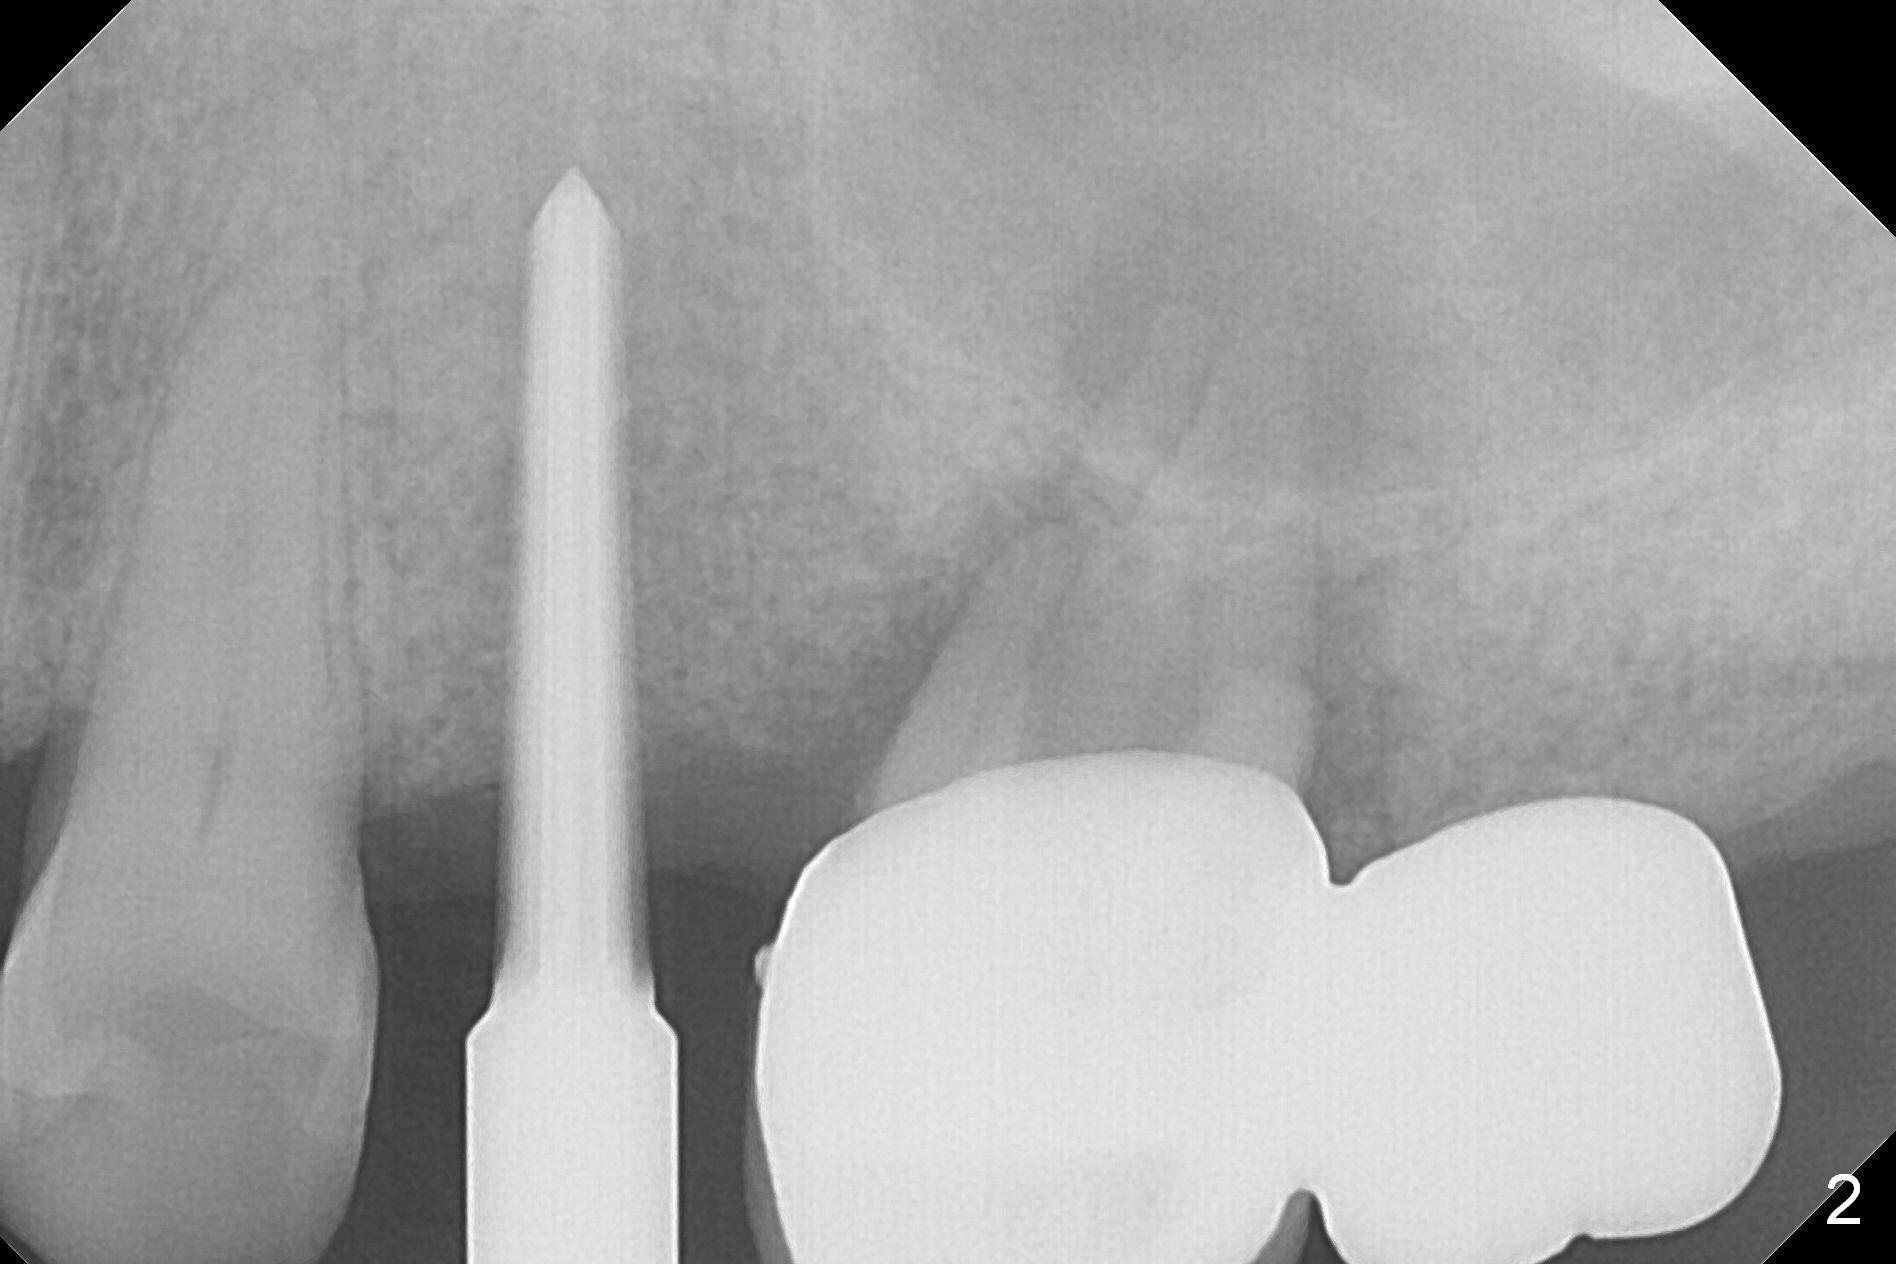

Osteotomy is initiated with Magic Split and a 1.6 mm drill at #13 before #14/15 cantilever bridge is removed (Fig.1). The trajectory is to be corrected (black line) in case an implant is placed at #14. After using Lindamann bur and reusing the 1.6 mm drill, a 3 mm Magic Expander is tapped in for 15 mm with ideal trajectory (Fig.2).